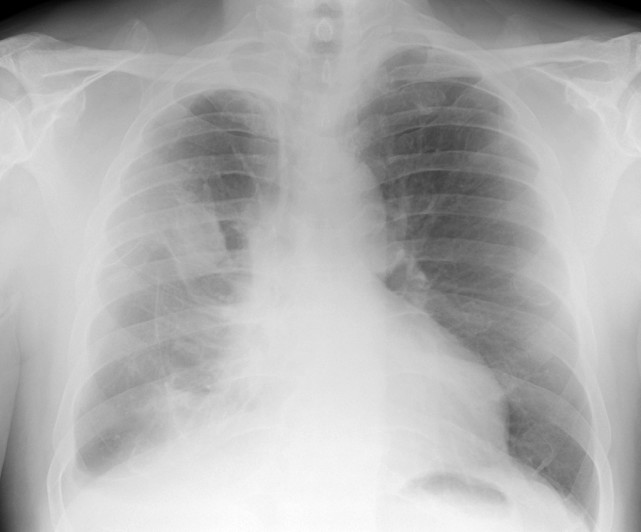

缓慢发生的小面积肺不张通常无症状,多数患者是在体检时,通过胸部X线片或胸部CT发现。

如果是比较严重的肺不张,表现可以包括:胸闷、气急、呼吸困难、刺激性干咳、口唇、指甲等发紫(紫绀)、发热。